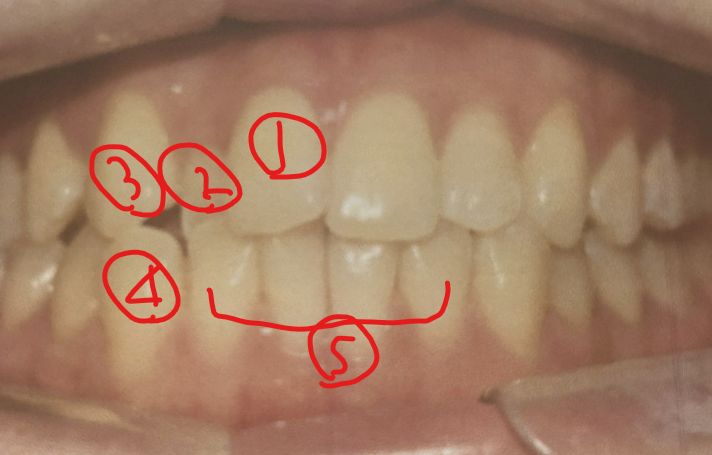

-> 사진상으로 윗니 1,2,3 아랫니 4, 5가 부분교정시 가지런하게 될 부분입니다. 특히 3,4는 송곳니로서 1,2,5 치아 바르게 되는것보다 시간이 더 많이 소요됩니다.

1,2,5바르게 하는것은 5개월이면 충분하지만, 3,4가 바르게 같이 되야되므로-송곳니가 앞니 치아중 뿌리가 가장길고 굵어서 교정시 치료기간이 상대적으로 많이 소요됩니다.-6-8개월소요됩니다.